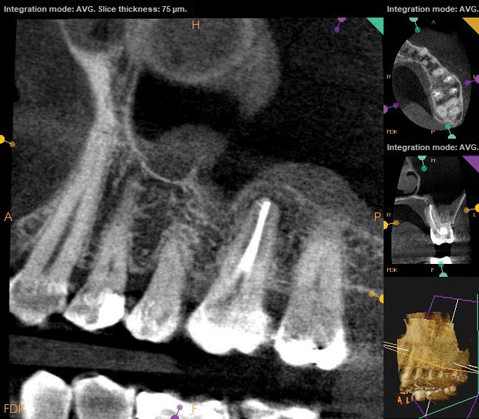

As part of the endodontic evaluation, CBCT imaging showed periapical pathology associated with tooth No. 14 as well as significant MSEO (Figure 7 and Figure 8). Clinical testing confirmed the absence of a cold response but no tenderness to percussion or palpation. A composite buildup was in place, absent evidence of recurrent decay. Soft tissues were unremarkable.

Fig 7 and Fig 8. Preoperative CBCT scans showing evidence of periapical pathology on tooth No. 14 as well as communication with the adjacent maxillary sinus and associated mucositis. Fig 7: Sagittal view, buccal roots No. 14. Fig 8: Sagittal view, palatal root No. 14.

Fig 8. Preoperative CBCT scans showing evidence of periapical pathology on tooth No. 14 as well as communication with the adjacent maxillary sinus and associated mucositis. Fig 7: Sagittal view, buccal roots No. 14. Fig 8: Sagittal view, palatal root No. 14.